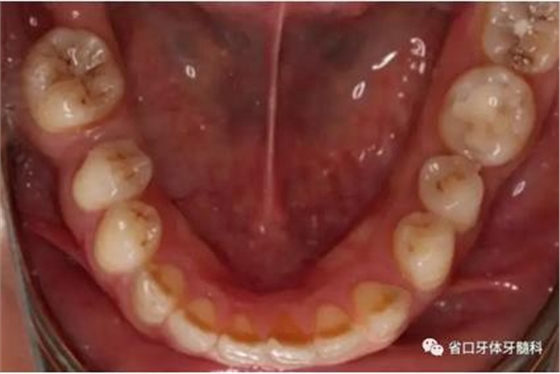

1.?病例簡介 43歲女性患者,主拆:右上前牙松動不適數(shù)日要求修復(fù)。現(xiàn)病史:患者數(shù)年前右上前牙因“齲壞”于外院行根管治療(具體不詳),數(shù)日前牙冠松動不適,現(xiàn)覺影響咀嚼及美觀,遂來我院要求進(jìn)一步診治。否認(rèn)高血壓、心臟病等重大疾病,否認(rèn)結(jié)核、肝炎等傳染病史,否認(rèn)手 術(shù)、輸血史等,未發(fā)現(xiàn)藥物過敏。無吸煙習(xí)慣。臨床檢查:口外觀顏面基 本對稱,皮膚無紅腫破潰,顳下頜關(guān)節(jié)區(qū)無彈響、雜音、壓痛,開口度約 37mm,開口型“↓”,頜下、刻下和頸部未及腫大淋巴結(jié)。中位笑線??趦?nèi)檢查,口腔衛(wèi)生可,色素(+),BOP(-),PD=2mm,上頜右側(cè)中切 牙冠部變色,冠根折斷至齦下3mm,叩不適,松動Ⅱ°~Ⅲ°。牙齦稍紅, 齦緣水平及齦乳頭高度可,屬于中厚齦生物型,附著齦寬度約5mm,唇系帶附著可。上頜右側(cè)中切牙缺牙間隙與對側(cè)同名牙一致,約>7mm,修復(fù)空 間良好。與對頜牙覆合覆蓋正常。MCT檢查示上頜右側(cè)中切牙冠根折斷至骨 下,根管內(nèi)見充填物,根充不全,根尖見陰影,大小約3mm×3mm。牙槽窩根方可用骨量可,唇側(cè)骨壁完整,冠方骨壁厚度約1mm。

圖1 術(shù)前口內(nèi)照

圖2 術(shù)前口內(nèi)照

圖3 術(shù)前口內(nèi)照